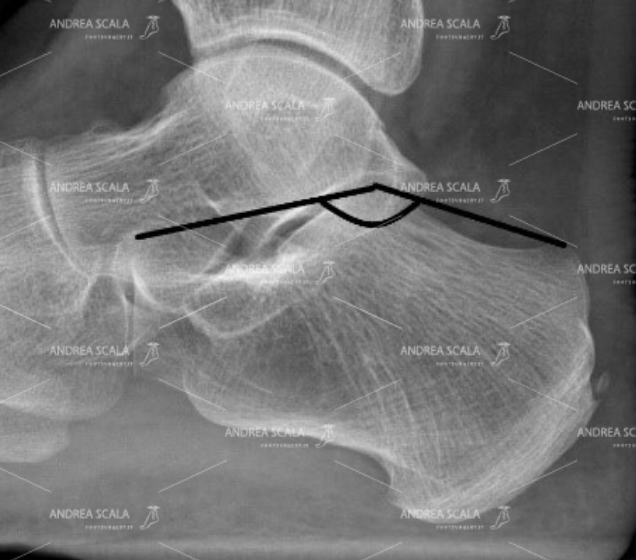

L’articolazione normale del calcagno si dispone con un angolo a vertice dorsale di 40 gradi (angolo di Bohler). Il radiologo e l’ortopedico dovrebbero riconoscere l’anatomia normale del calcagno.

La Radiografia del piede fratturato è importante per mostrare che il calcagno non è normale, ma non è sufficiente. Quando si sospetta la frattura del calcagno occorre fare la TAC. La TAC mostra con precisione che dopo la frattura il calcagno è schiacciato, l’angolo di Bohler è appiattito, l’articolazione è spezzata, si vedono bene i frammenti della frattura.

La Radiografia non è sufficiente per capire la gravità della frattura del calcagno. E’ necessario fare la TAC. Dopo la frattura il calcagno è schiacciato, l’angolo di Bohler è appiattito, l’articolazione è spezzata, si vedono bene i frammenti della frattura.